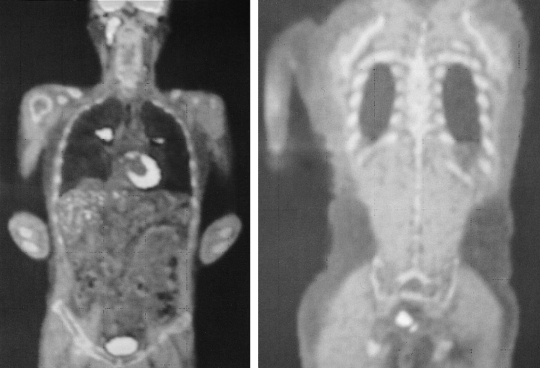

Figure 2

PET-CT revealed hypermetabolic lesions of the head, neck, mediastinal lymph node, lung and rectum.